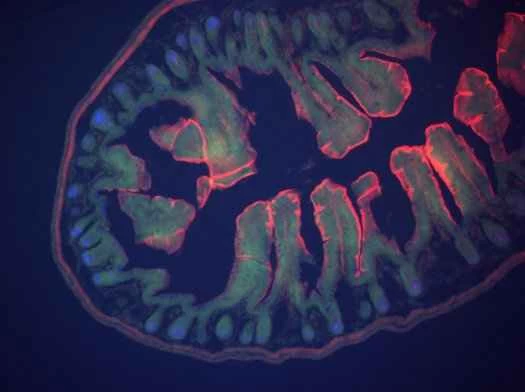

私たちは生物医学や工学を頻繁に取り上げていますが、時々こんな疑問が湧きます。もし私が、おそらくは恐ろしい手足切断や内臓損傷の事故に遭ったために、もろい肉体を再構築し、手足、関節、感覚、臓器を最先端のバイオニクス機器に置き換えるとしたら、一体何を手に入れるのだろうか?オリンピックレベルのレースで短距離走者が使うような人工下肢が欲しいだろうか?それとも、自然な脚と同じように坂を登れる電動の脚が欲しいだろうか?私は、自分が身に着けたい、あるいは装着したいバイオニックボディパーツを15個リストアップしました。

これらの身体部位の中には、既に利用可能で、命を救ったり、生活を楽にしたりするものもあれば、プロトタイプや概念実証の段階に過ぎないものもある。既存の身体部位を可能な限り犠牲にすることなく置き換えるように設計されたものもあれば、生身の肉体よりも優れた利点をもたらすものもある。これがバイオニクスの現状、そして近未来の姿である。